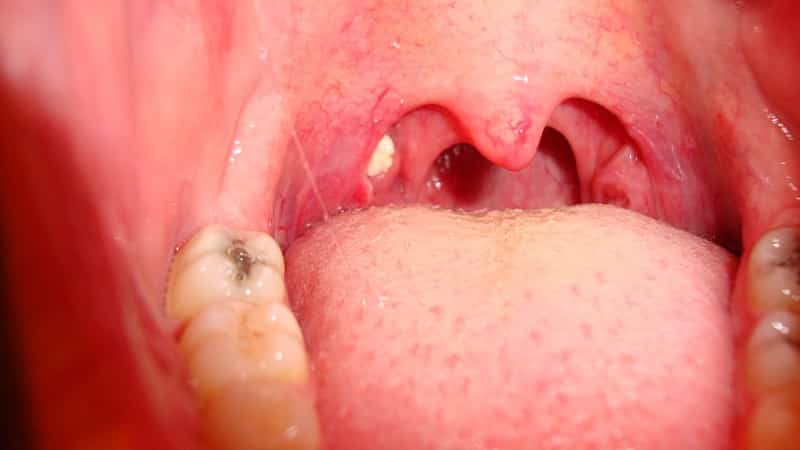

Появление на поверхности этого органа микробного налета, гнойных бляшек или красных воспаленных очагов говорит о том, что на слизистой наблюдается инфекционное, бактериальное или грибковое поражение, которое ухудшает структуру лимфоидной ткани.

В это же время врач уделяет внимание не только местоположению налета и бляшек, но также их структуре, плотности, глубине проникновения, оттенку и т.д. По указанным выше характеристикам доктор может точно определить причину возникновения образований и выписать эффективную терапию.

Появление на гландах белых пятен говорит о том, что на слизистой наблюдается инфекционное, бактериальное или грибковое поражение

Давайте рассмотрим, о каких патологиях и болезнях могут свидетельствовать белые и красные пятна на миндалинах.

- Острый и хронический тонзиллит. Пожалуй, самая распространенная причина появления на гландах белых точек. По сути, заболевание представляет собой воспаление гланд на фоне деятельности патологической микрофлоры. Острая гнойная форма характеризуется накоплением гноя в лакунах (складках) миндалин. Внешне это напоминает плотные белые и желтоватые пробки, которые легко удаляются с помощью ватного тампона. Хроническая форма подразумевает постоянное присутствие небольших пробок, которые следует периодически самостоятельно удалять и полоскать горло. Других симптомов в этой форме, как правило, не наблюдается.В случае появления ангины на фоне тонзиллита у пациента краснеет и воспаляется горло, появляется болезненность при общении и глотании, резко растет температура, гнойники увеличиваются в объеме и становятся потенциальными источниками разнесения инфекции по организму.

Гнойные пробки в медицине носят название тонзиллолиты. Они представляют собой бело-желтые камни, образовавшиеся в лакунах. По структуре могут быть мягкими либо плотными (при отложении солей), их размер достигает от 1 мм до нескольких сантиметров, имеют специфический запах, что вызывает дискомфорт у пациента.

Несмотря на то, что хронический тонзиллит зачастую развивается у мужского населения, выявить это заболевание у себя может практически каждый человек. У ребенка на горле белые комочки также свидетельствуют о хроническом тонзиллите, который может поражать организм уже с двухлетнего возраста. На фото ниже можно увидеть, какой вид имеют белые комочки, образовавшиеся на миндалинах (см. Миндалины в горле: как возникает воспаление): Белый комочек в горле свидетельствует о заполнении лакун миндалин бактериями Тонзиллит может проявляться такими симптомами:

При осмотре без специальных приборов можно увидеть лишь незначительную часть ротоглотки. При инфекционных поражениях белые пятна в горле обычно затрагивают заднюю стенку горла, располагаются на миндалинах, небных дужках. Исключением является дифтерия и некоторые инфекции атипичной локализации.